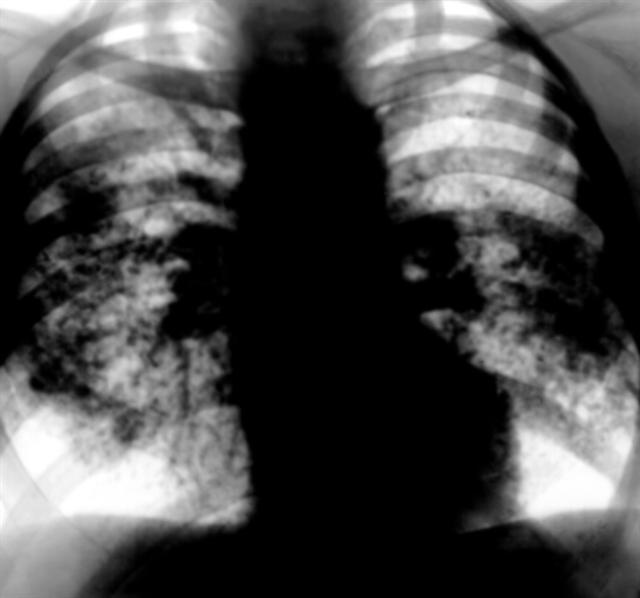

Рис. 4. Рентгенограмма грудной клетки при саркоидозе легких и внутригрудных лимфатических узлов: расширенные тени легочных корней формируются в основном увеличенными лимфатическими узлами, в средних и частично в нижних легочных полях видны множественные, местами сливающиеся очаговоподобные тени (картина диссеминации); прозрачность легких в области верхушек сохранена.